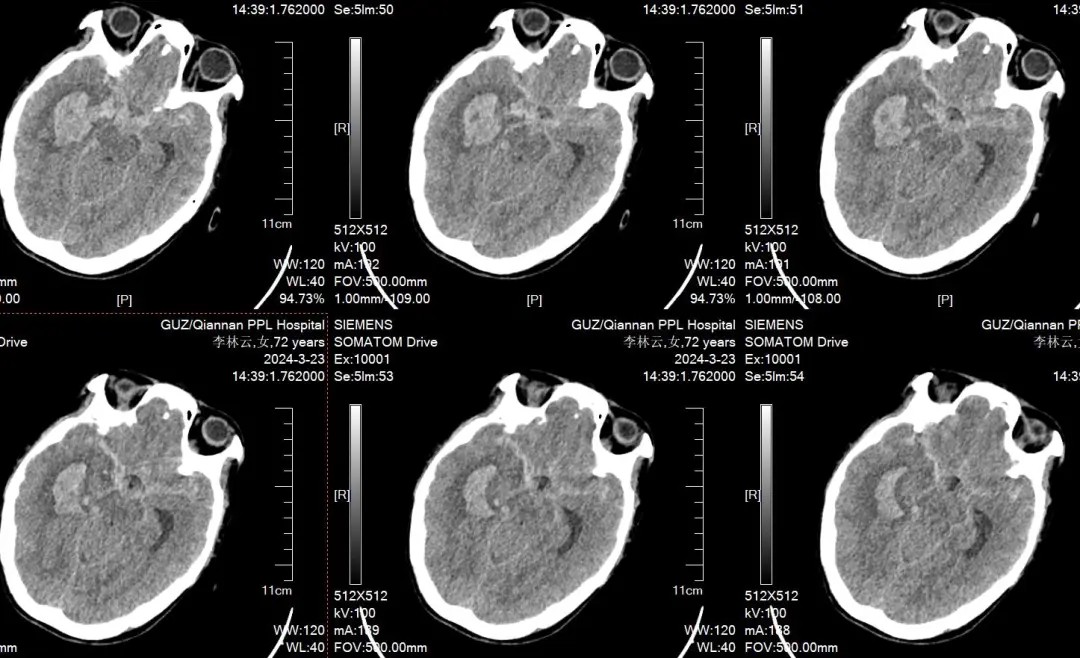

来自平塘县72岁的李姥姥,因突发剧烈头痛伴意识障碍7小时入院黔南州人民医院神经外科。行头颅CT平扫提示典型蛛网膜下腔出血,高度怀疑颅内动脉瘤破裂出血所致,脑血管成像(CTA)证实为右侧后交通微小动脉瘤破裂。情况紧急需马上手术干预治疗。

因为动脉瘤位置特殊,且动脉瘤微小,小于3mm,瘤颈宽,需要支架辅助弹簧圈栓塞这个微小破裂的颅内动脉瘤,一期行脑室外引流,目的是引流血性脑脊液降低颅内压,有利于老太太术后度过危险期。各就各位,神经外科团队有条不紊地做着各项术前准备,最终科室顺利完成了四级高难度手术,术后第二天李姥姥意识即有明显改善,由昏睡转为嗜睡。

针对李姥姥术后恢复情况,神经外科团队联合临床营养科制定了快速康复的诊疗方案。因患者颅内动脉瘤破裂伴蛛网膜下腔出血且高龄、意识不清、长期卧床有肺部感染、消瘦、贫血等多个问题,医务人员给予纠正贫血、抗生素保护下进行俯卧位通气、量身定制营养餐、血性脑脊液置换避免发生脑积水、早期下床康复活动等快速康复治疗。李姥姥顺利度过危险期,无继发脑积水,术后7天拔除脑室引流管,术后13天复查头颅CT平扫提示蛛网膜下腔出血已吸收,意识完全清醒,无神经外科功能损害表现,16天就达到治愈出院标准。

术后13天复查头颅CT平扫提示蛛网膜下腔出血已吸收